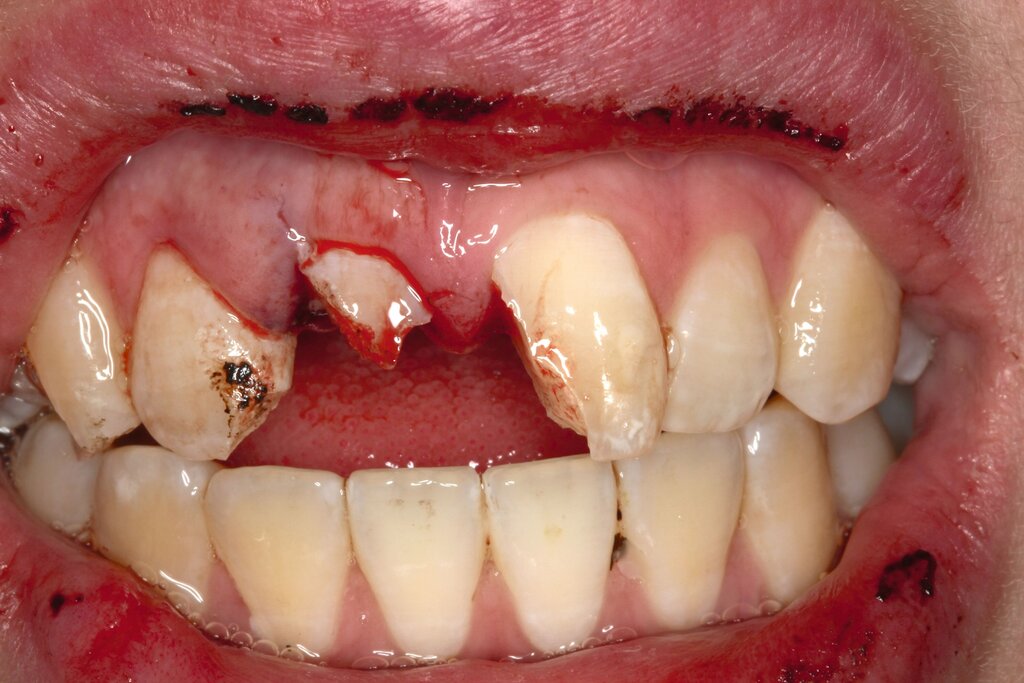

Die adhäsive Wiederbefestigung mitgebrachter Kronenfragmente bietet sich als einfache und konservative Methode zur Wiederherstellung von Funktion und Ästhetik an (Abbildung 1). Wenn das Fragment nach dem Unfall unter feuchten Bedingungen gelagert wurde, wird die Wiederbefestigung idealerweise sofort während der Notfallbehandlung durchgeführt. Wurde das Fragment jedoch durch eine längere Trockenlagerung dehydriert, sind sowohl das ästhetische Ergebnis als auch die Komposithaftung kompromittiert. In solchen Fällen wird eine Lagerung in physiologischer Kochsalzlösung oder in Wasser für einen Tag empfohlen, um eine Rehydrierung des Fragments zu ermöglichen [Farik et al., 1999], während das Dentin in der Zwischenzeit mit einem leicht entfernbaren temporären Material bedeckt ist (zum Beispiel Kalziumhydroxid-Zement). Die Rehydrierungszeit kann durch eine feuchte Lagerung des Fragments in einem sauberen Drucktopf auf 30 bis 60 Minuten verkürzt werden.